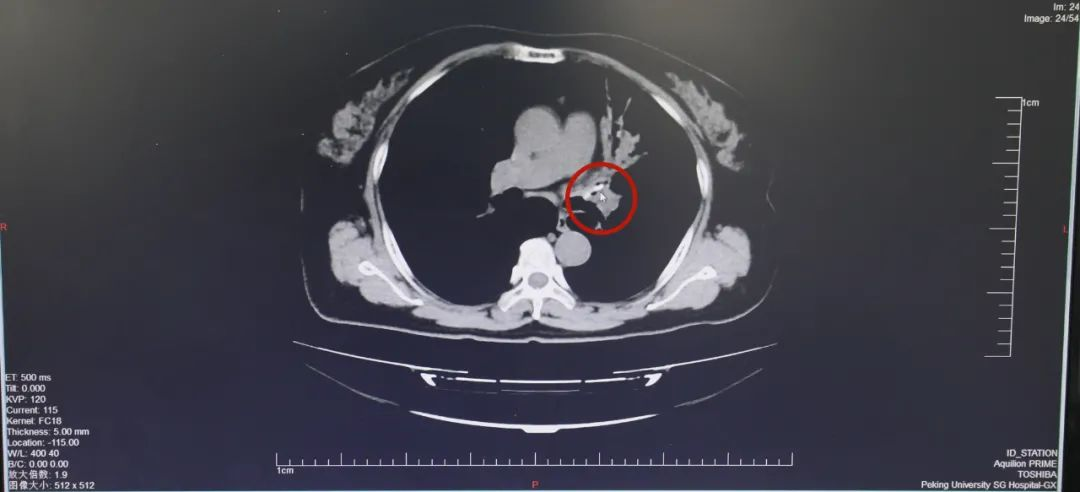

问清楚了之前的病史,向主任仔细察看肺部CT影像:肺部有明显炎症表现,结合患者血常规白细胞增高,符合肺炎的诊断,但是这小一块,似乎不太对?

在呼吸医学领域深耕30年有余,向主任早已练就了一双慧眼,指着CT图像给大家示意。

肺部CT扫描是根据人体的密度不同,通过X线影像断层一层、一层地把人体的结构展现在片子上,而郝阿姨左上肺CT影像上,有一小块极其细微的黑影,密度偏高。

气管异物影像

这说明,气管有异物!